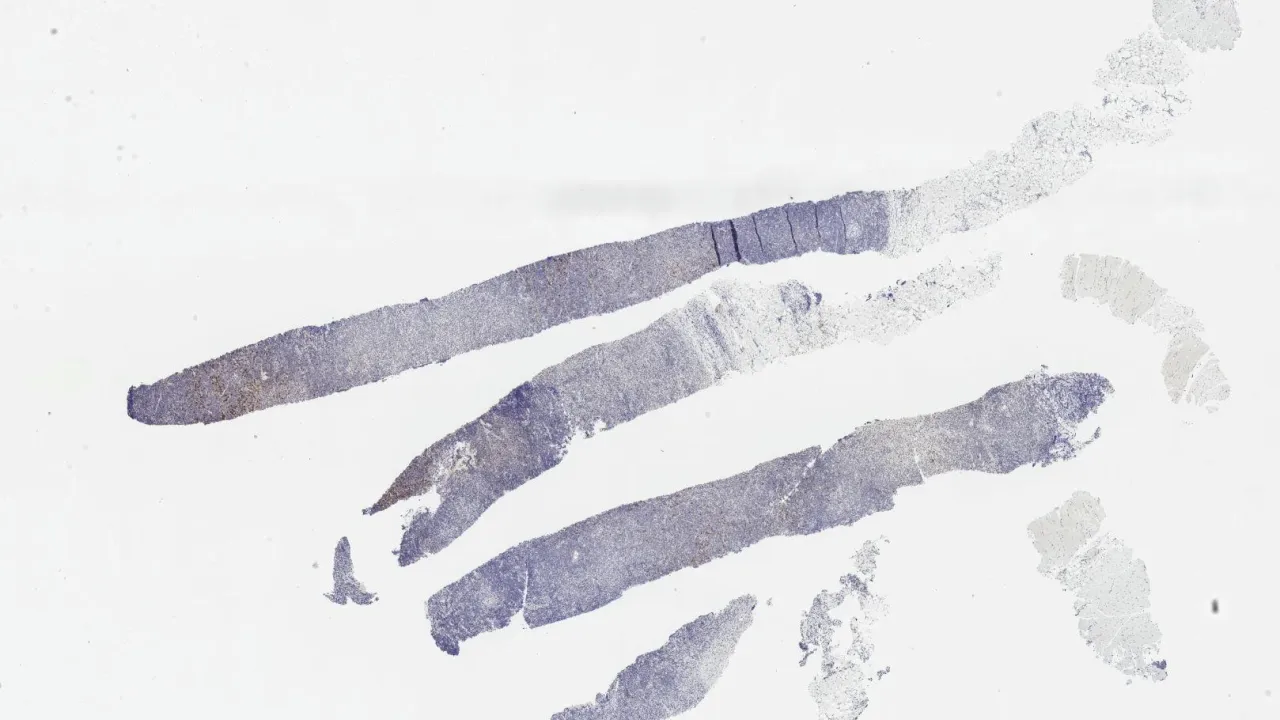

Soft Tissue, Subcutaneous panniculitis-like T-cell lymphoma, CD7 stain